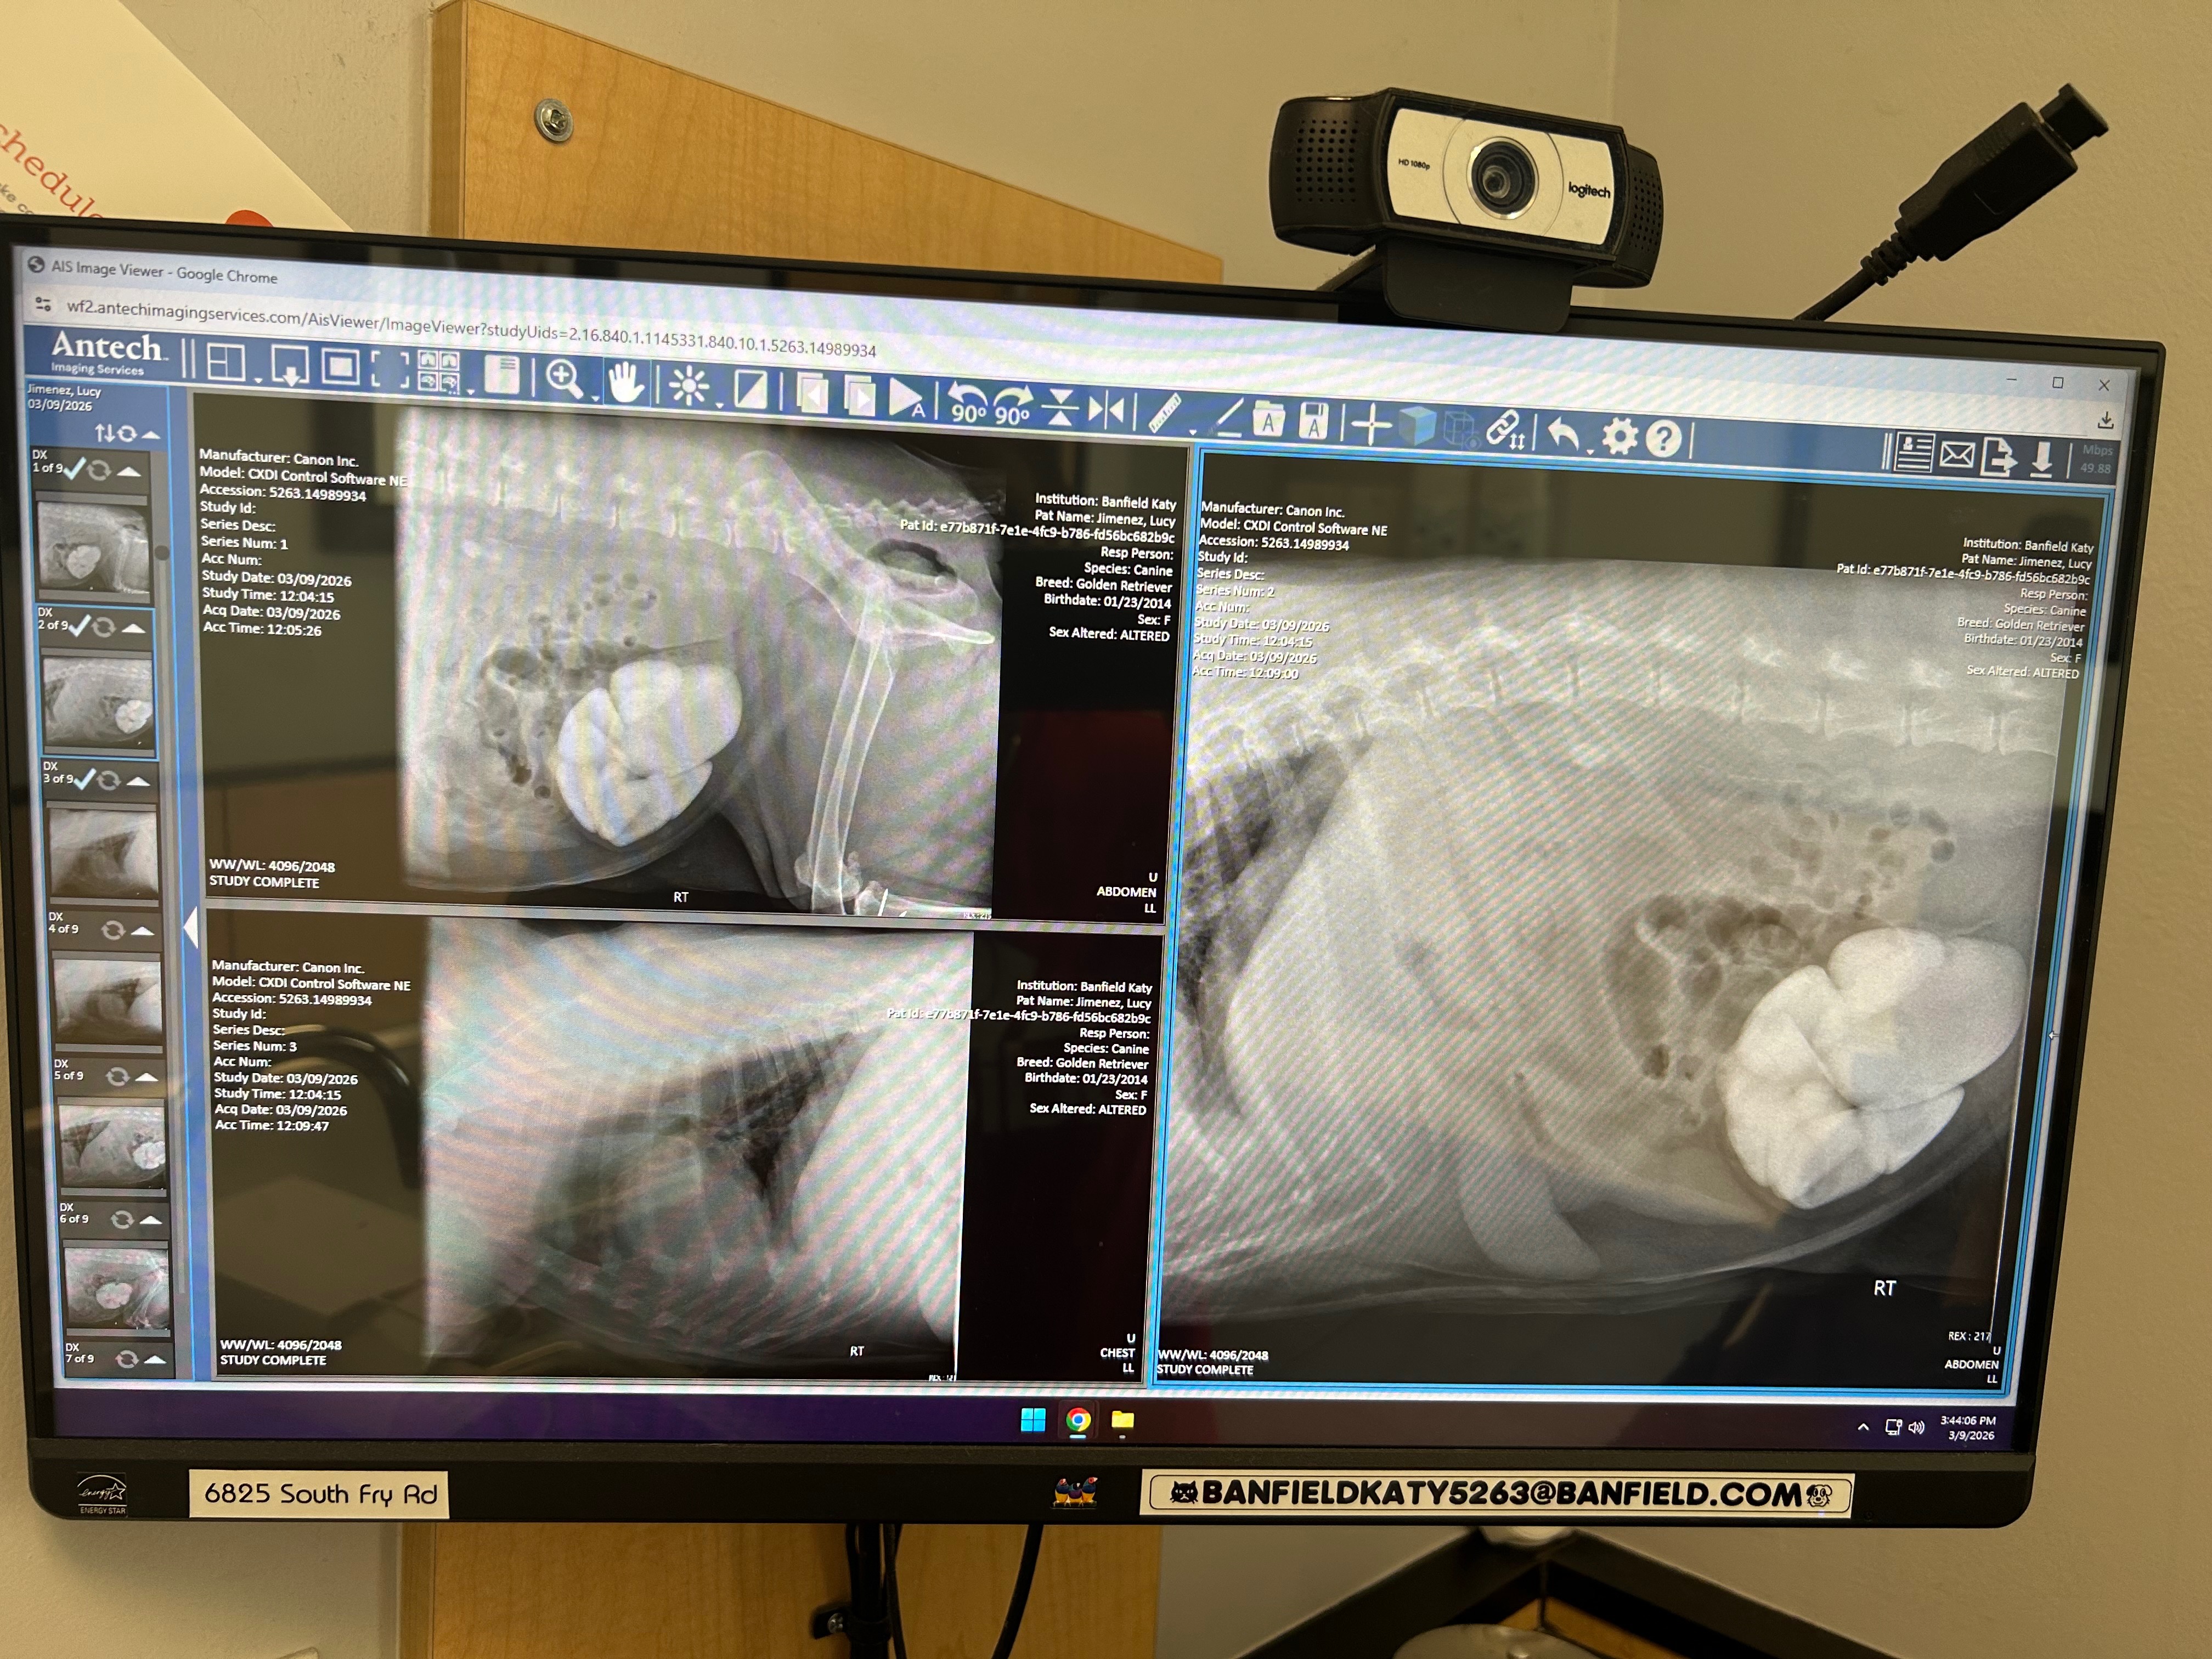

My name is Nancy, and my dog Lucy is truly my best friend and constant companion. She means everything to me—she’s my family, my comfort, and my joy. Recently, Lucy became very sick. I noticed blood in her urine and rushed her to see Dr. Cornelius at Banfield for an evaluation. The veterinarian took the time to explain Lucy’s condition to me, and I learned that she has bladder stones and blood in her urine, which is causing her a lot of pain. It’s even become difficult for her to go to the bathroom, and seeing her struggle breaks my heart.